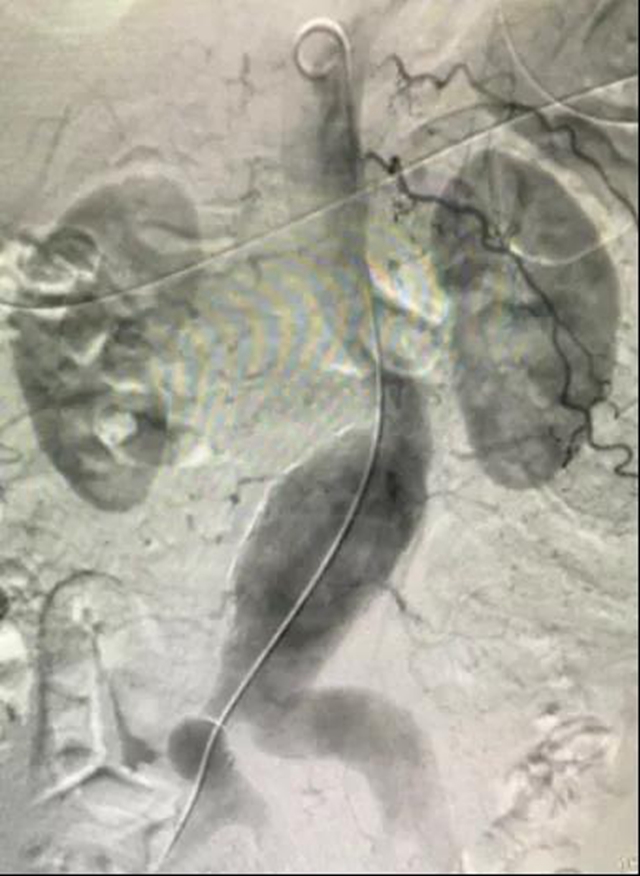

手术中

患者为78岁女性,因腹痛入院。行腹部CTA检查提示:腹主动脉中下段及双侧髂总动脉动脉瘤,腹主动脉及双侧髂动脉壁钙化。

4月15日上午,钟武院长亲自主持手术。经过手术室·麻醉科团队的共同努力,气管插管全麻成功后,在肝胆胰脾·血管外科、介入导管室组成的治疗团队配合下,进行了腹主动脉及双侧髂总动脉瘤血管腔内修复术+左侧髂内动脉栓塞术。

支架置入前

该手术通过腹股沟处的股动脉运用导丝导管技术,在穿刺孔将封装压闭的人工血管支架输送到瘤体位置,然后进行释放锚定,血流将通过人工血管走行。在紧张有序的氛围下,手术取得了圆满成功。